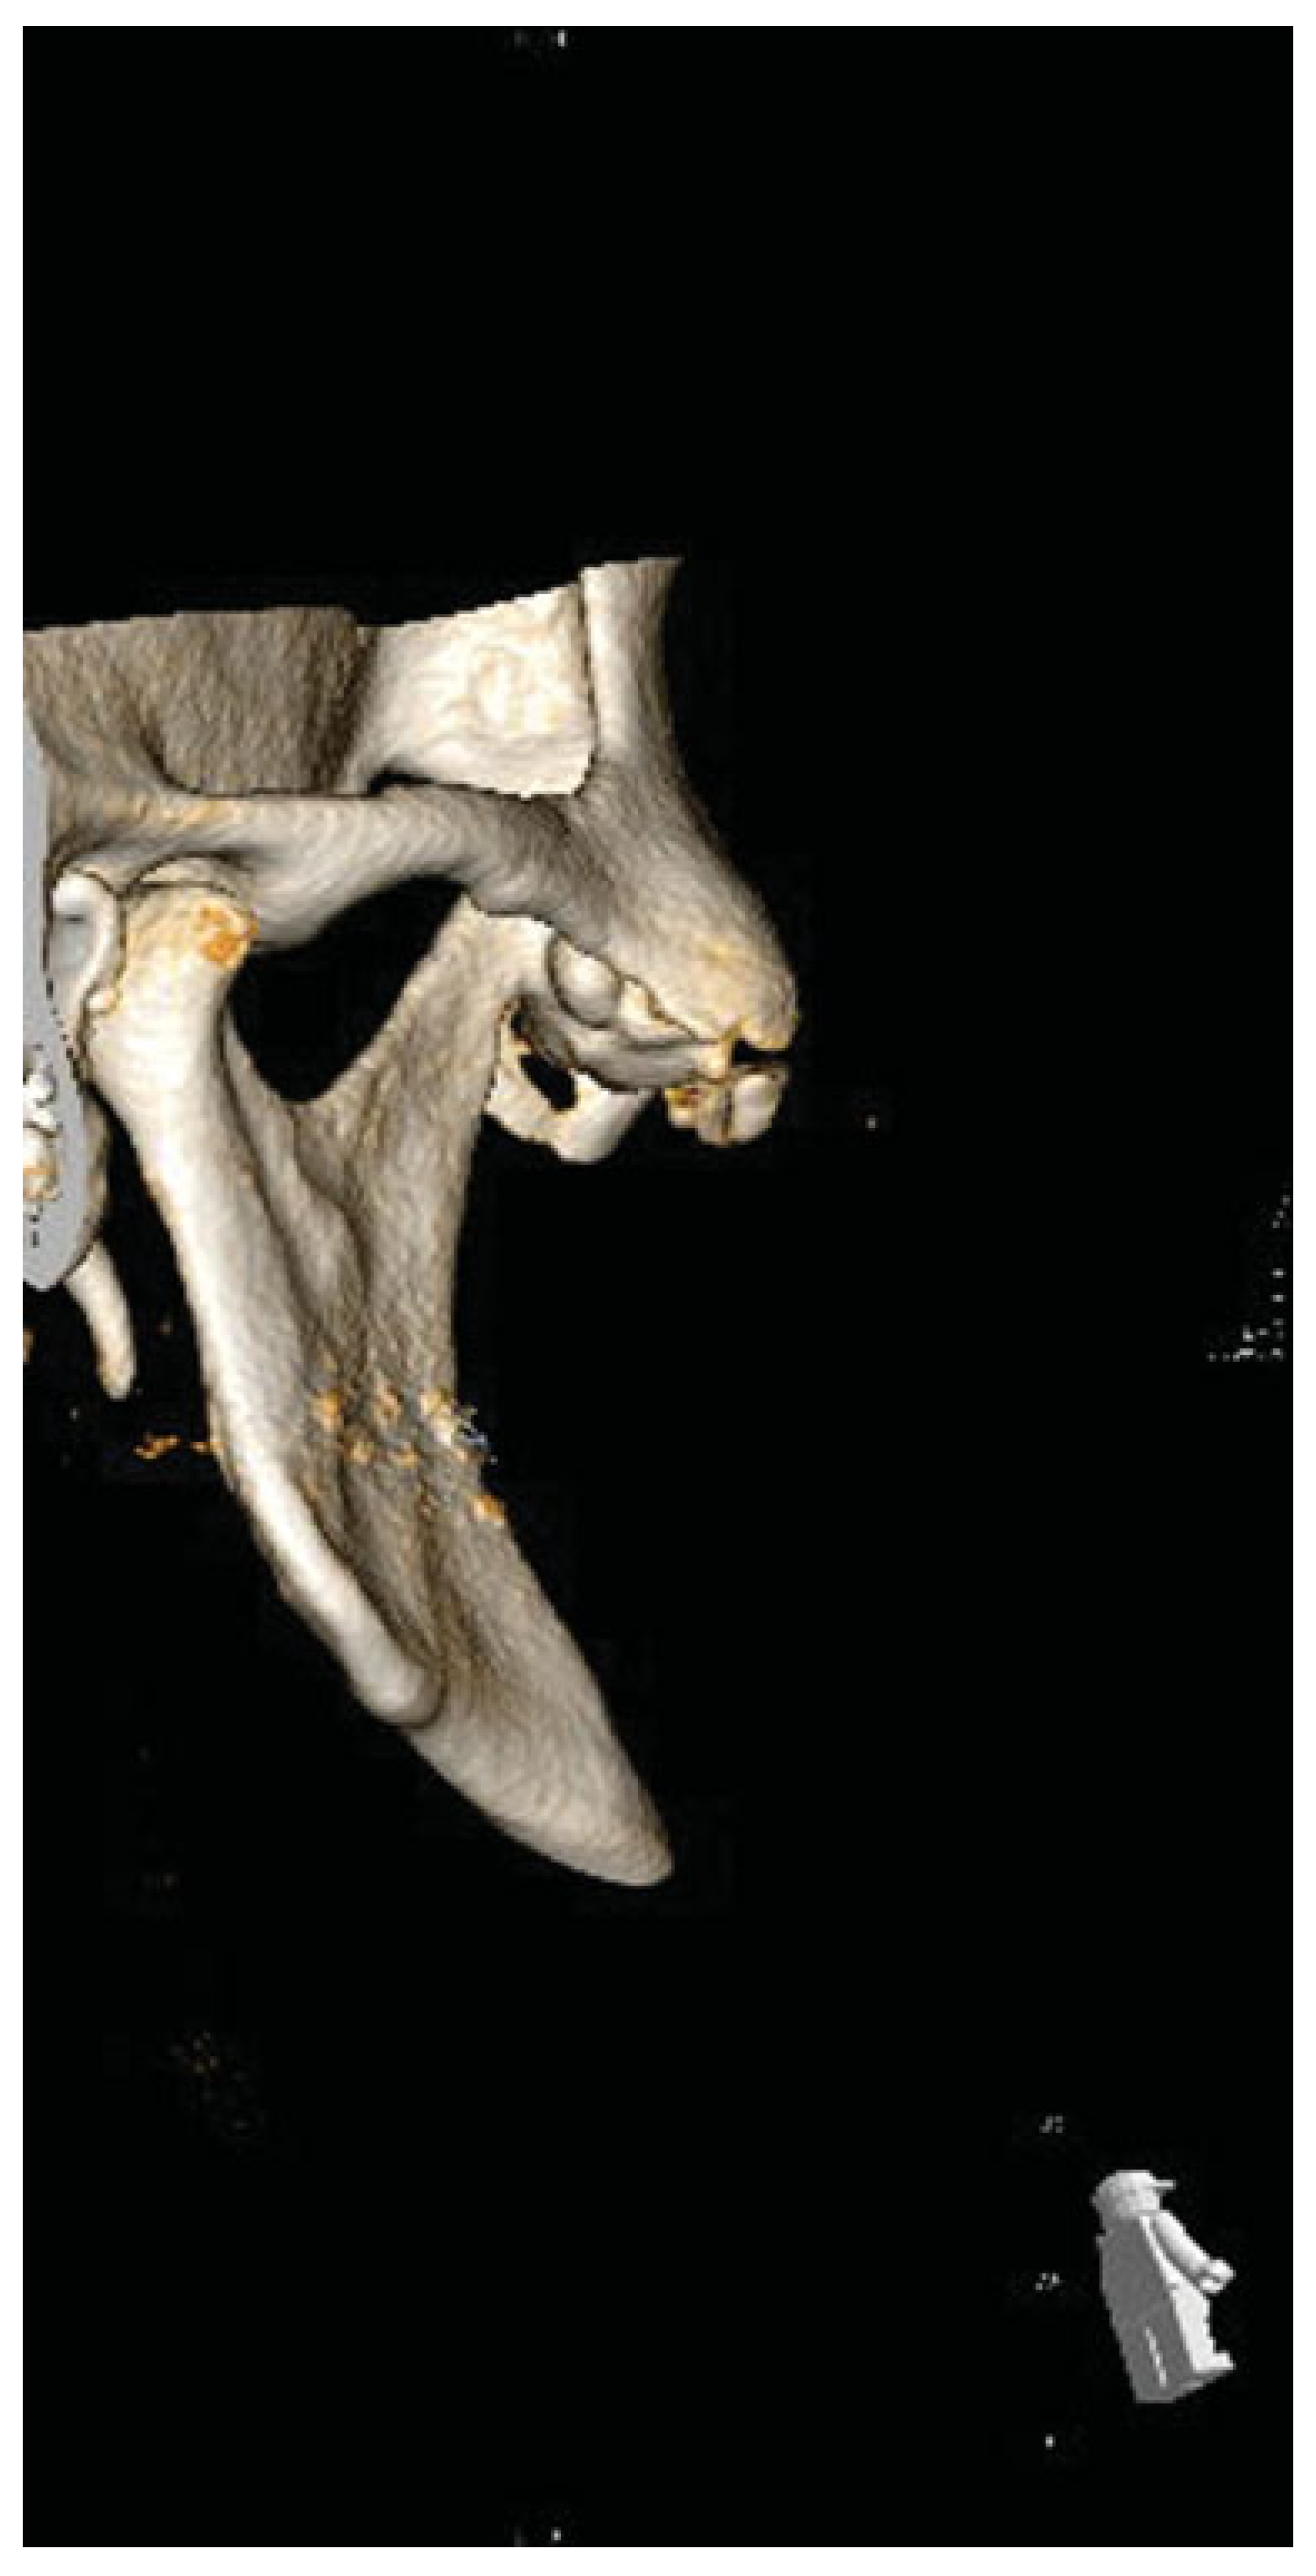

Osteochondroma of Coronoid Process: A Rare Etiology of Jacob Disease

Case Report